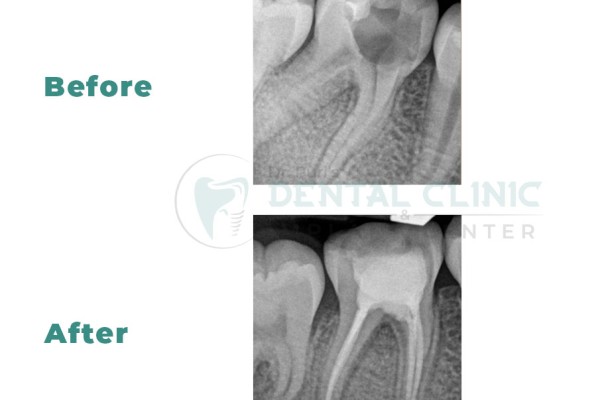

Root canal treatment (RCT) is designed to eliminate bacteria from the infected root canal, prevent reinfection of the tooth and save the natural tooth. When one undergoes a root canal, the inflamed or infected pulp is removed and the inside of the tooth is carefully cleaned and disinfected, then filled and sealed.

After RCT , the tooth is restored with a crown or filling for protection and will continue to function like any other tooth.